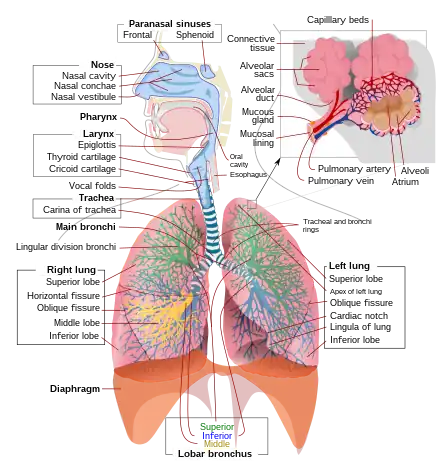

The following are images from various Medicine-related articles on Wikipedia.